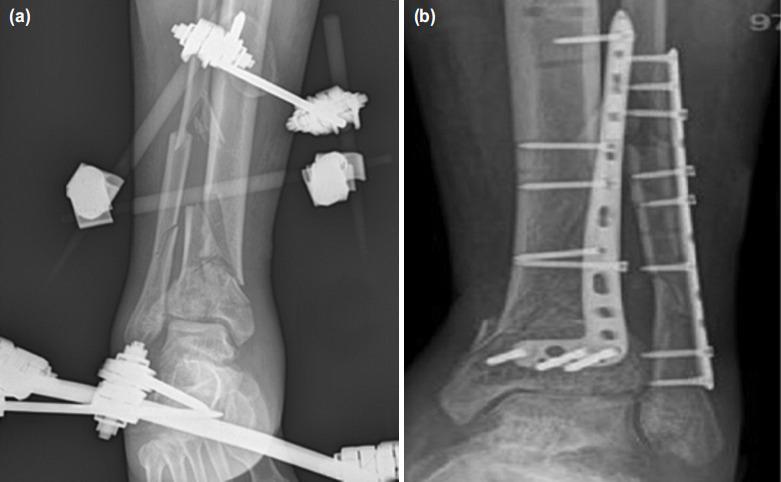

伴有软组织损伤的关节内胫腓骨远端骨折的两阶段手术治疗:初次手术时应在哪个阶段应用腓骨钢板?

Two-Stage Surgical Procedure in Intra-articular Distal Tibiofibular Fractures with Soft Tissue Injury: in Which Stage Should the Fibular Plate be Applied at Initial Surgery?

The selection of the stage where fibular plate was performed in two-stage surgery of the intra-articular distal tibiofibular fractures with soft tissue injury is still controversial. The aim of the study was to compare the complications, radiological and functional outcomes between the patients who had fibular plate at initial or second phase during surgical management of such fractures.

MATERIALS AND METHODS

In this study, medical records of 47 patients who underwent a two-stage surgical procedure for intra-articular distal tibia fractures accompanying soft tissue injury were retrospectively examined. Delta frame was applied in all cases within 24 hours following admission to the emergency department in accordance with AO principles. Those cases where fibular plate was applied during the initial stage and the second stage were classified as Group 1 and Group 2 in order to compare recorded data between the two groups.

RESULTS

According to the results of the study, there were 25 cases in Group 1 and 22 cases in Group 2 in which fibular plate was applied at the first stage and the second stage, respectively. The mean follow-up was found as 27.7±7.0 months in Group 1 and 28.2±6.2 months in Group 2 (p=0.778). No difference was found between the two groups in terms of the age, sex, hospital stay, the time between two surgical procedures, tibiofibular angle and AOFAS scoring (p>0.05).These two groups were also similar in mechanism of injury, Denise-Weber or AO classification, rates of tibiofibular malalignment on post-operative CT, fibular rotation, intra-articular tibial step-off, tibial varus-valgus duration of union, rate of infection, fibular angulation and the presence of the flap/graft/debridement (p>0.05).

CONCLUSION

In conclusion, two-stage surgical procedure in intra-articular distal tibiofibular fractures may be an effective method decreasing soft tissue complications. The timing of the open reduction and internal fixation of the fibula at different stages may not necessarily have an impact on the success of the post-operative tibial reduction, the total duration of surgery, syndesmosis malalignment or soft tissue complications.